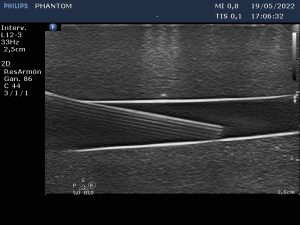

És per això que aquest mes de juny ha arrencat amb un ‘Curs de punció ecoguiada i dispositius d’accés vascular’, al Consell Comarcal de l’Alt Urgell, impartit per tres infermers, que a més són tècnics superiors en Imatge pel Diagnòstic, membres de l’Equip de Teràpia Intravenosa (ETI) de l’Hospital Universitari Arnau de Vilanova (HUAV) de Lleida. La punció ecoguiada és una tècnica gens invasiva que permet a la infermera veure, de forma clara i directa, l’estructura vascular a la qual ha d’accedir i col·locar l’agulla en el lloc més adient per inserir la via (catèter) o qualsevol altre dispositiu d’accés vascular (DAV), evitant incomoditats i complicacions pel pacient.

La col·locació de catèters intravenosos i altres dispositius d’accés vascular –perifèric curt, de línia mitjana, central d’inserció perifèrica (PICC) o d’inserció central (CVC)– requereix expertesa i tècnica de la infermera, tant en la punció com el manteniment. La tècnica Seldinger, metodologia concebuda inicialment per a la cateterització percutània dels vasos sanguinis, però molt estesa en l’actualitat per l’alt nivell d’evidència sobre la seva utilitat que rau en la reducció de l’índex de fracàs en la col·locació de les vies centrals, així com de les complicacions afegides; o el rentatge intraluminal ‘Push-Stop-Push’ amb pressió positiva, que recomana la instil·lació dels catèters PICC amb sèrum salí fisiològic a embolades, per generar turbulències i garantir la neteja de les parets del dispositiu, com a tècnica de manteniment; han estat altres dels temes tractats.